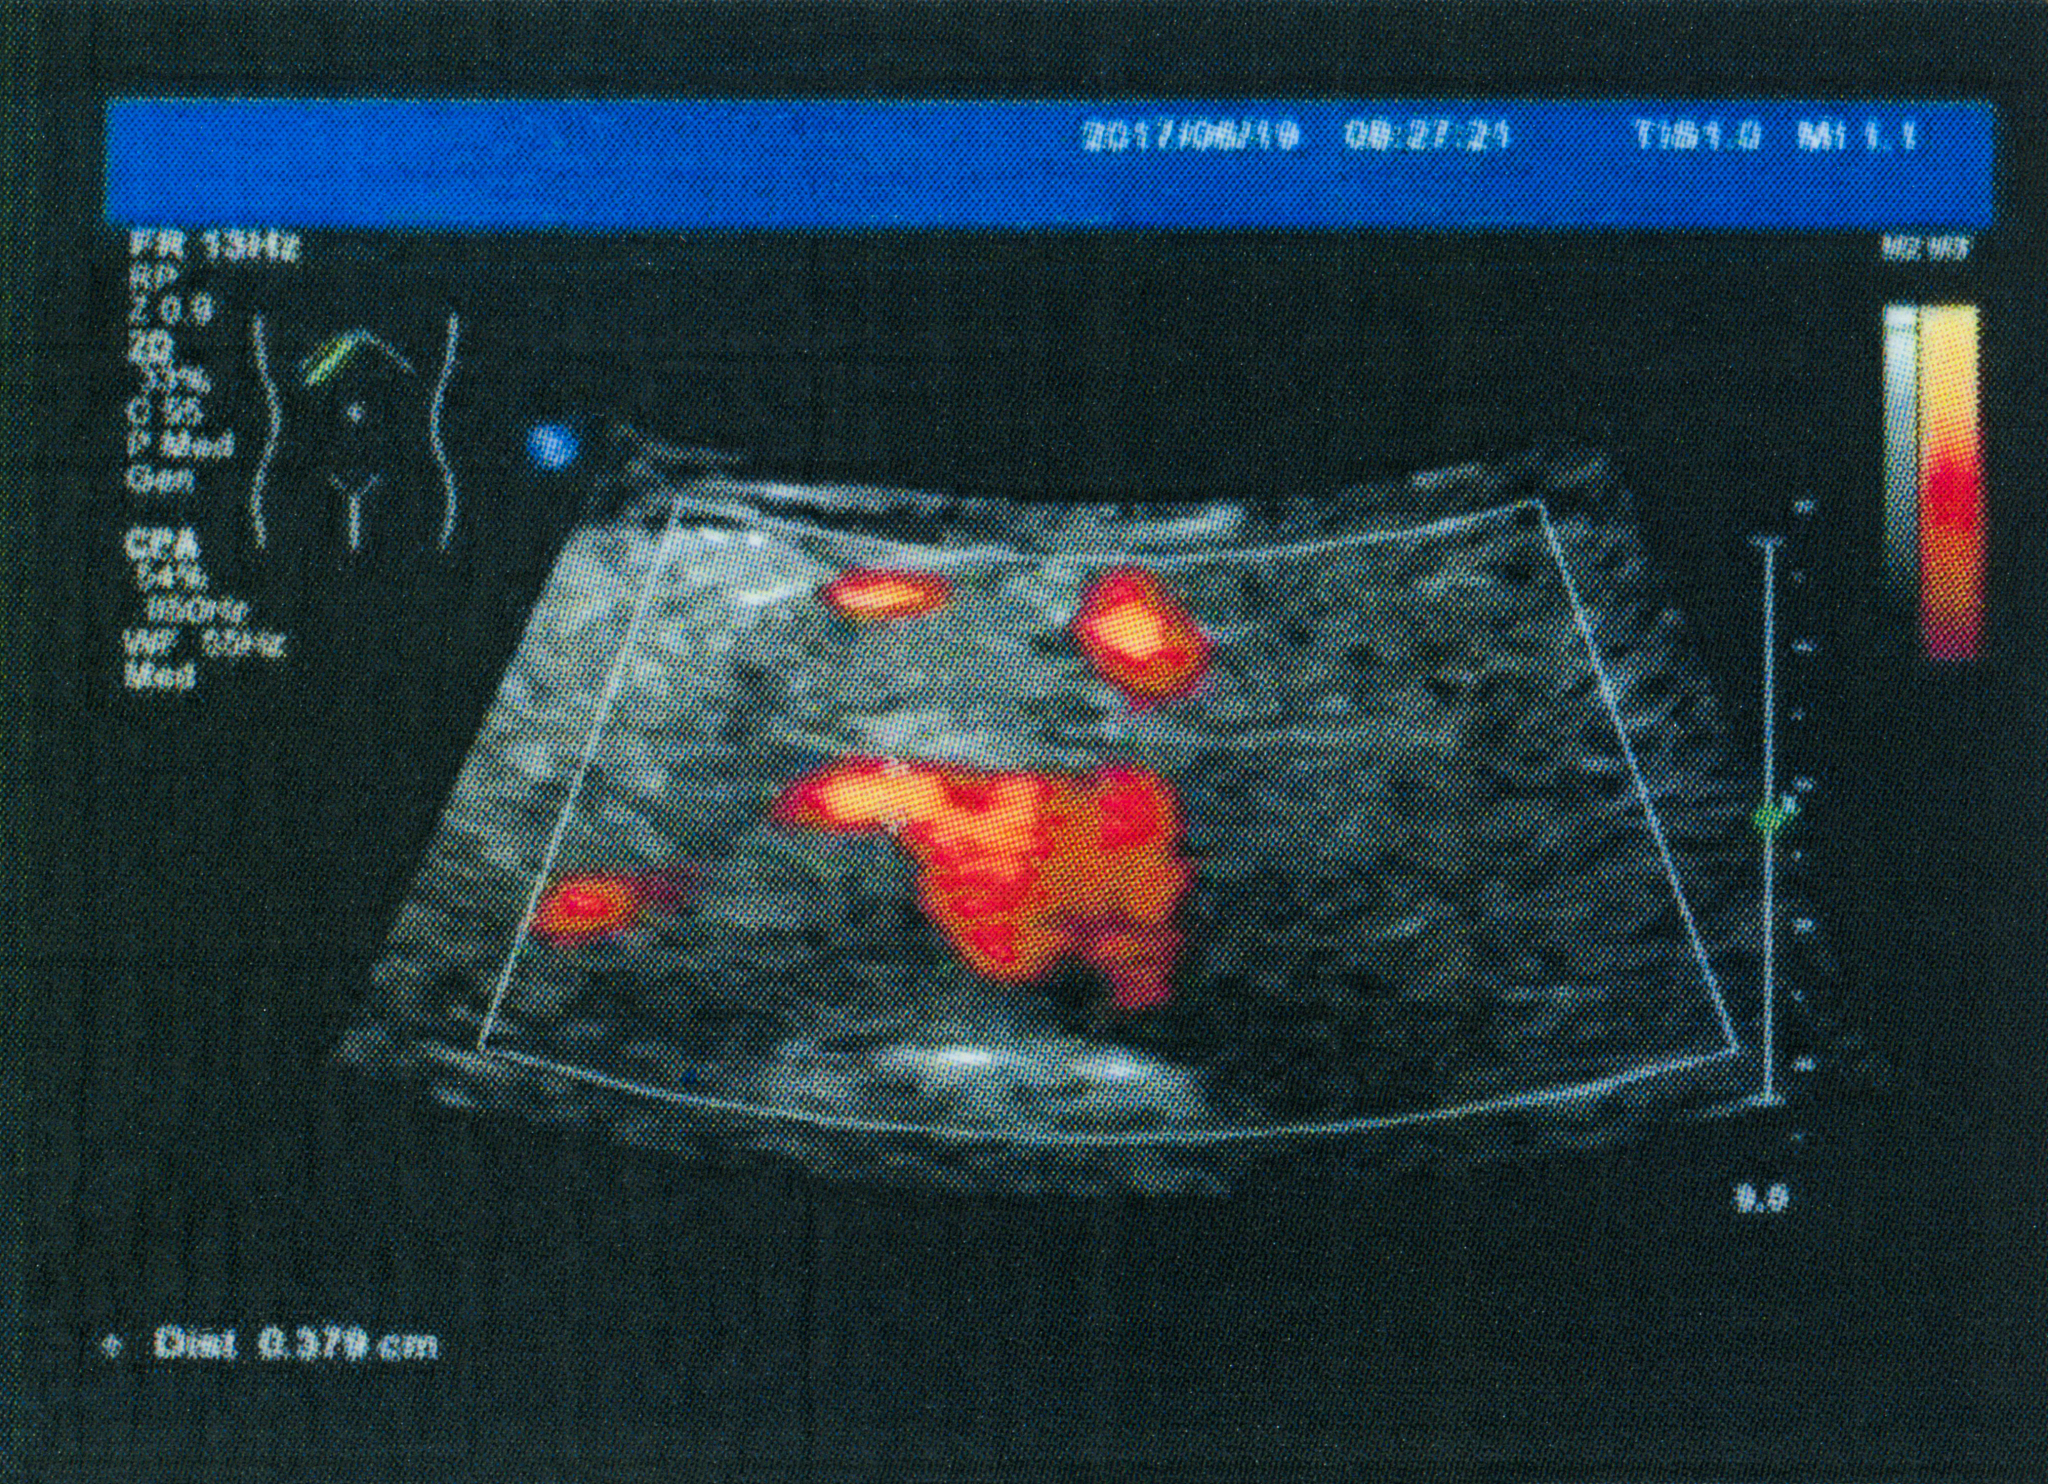

为进一步明确诊断,经过患者知情同意进行了超声造影检查,显示稍低回声的斑块内存在大量新生血管(图1),伴随着斑块局部纤维帽的不连续,宽度约为1.4mm,深度约为4.0mm,并充满造影剂(图2)。